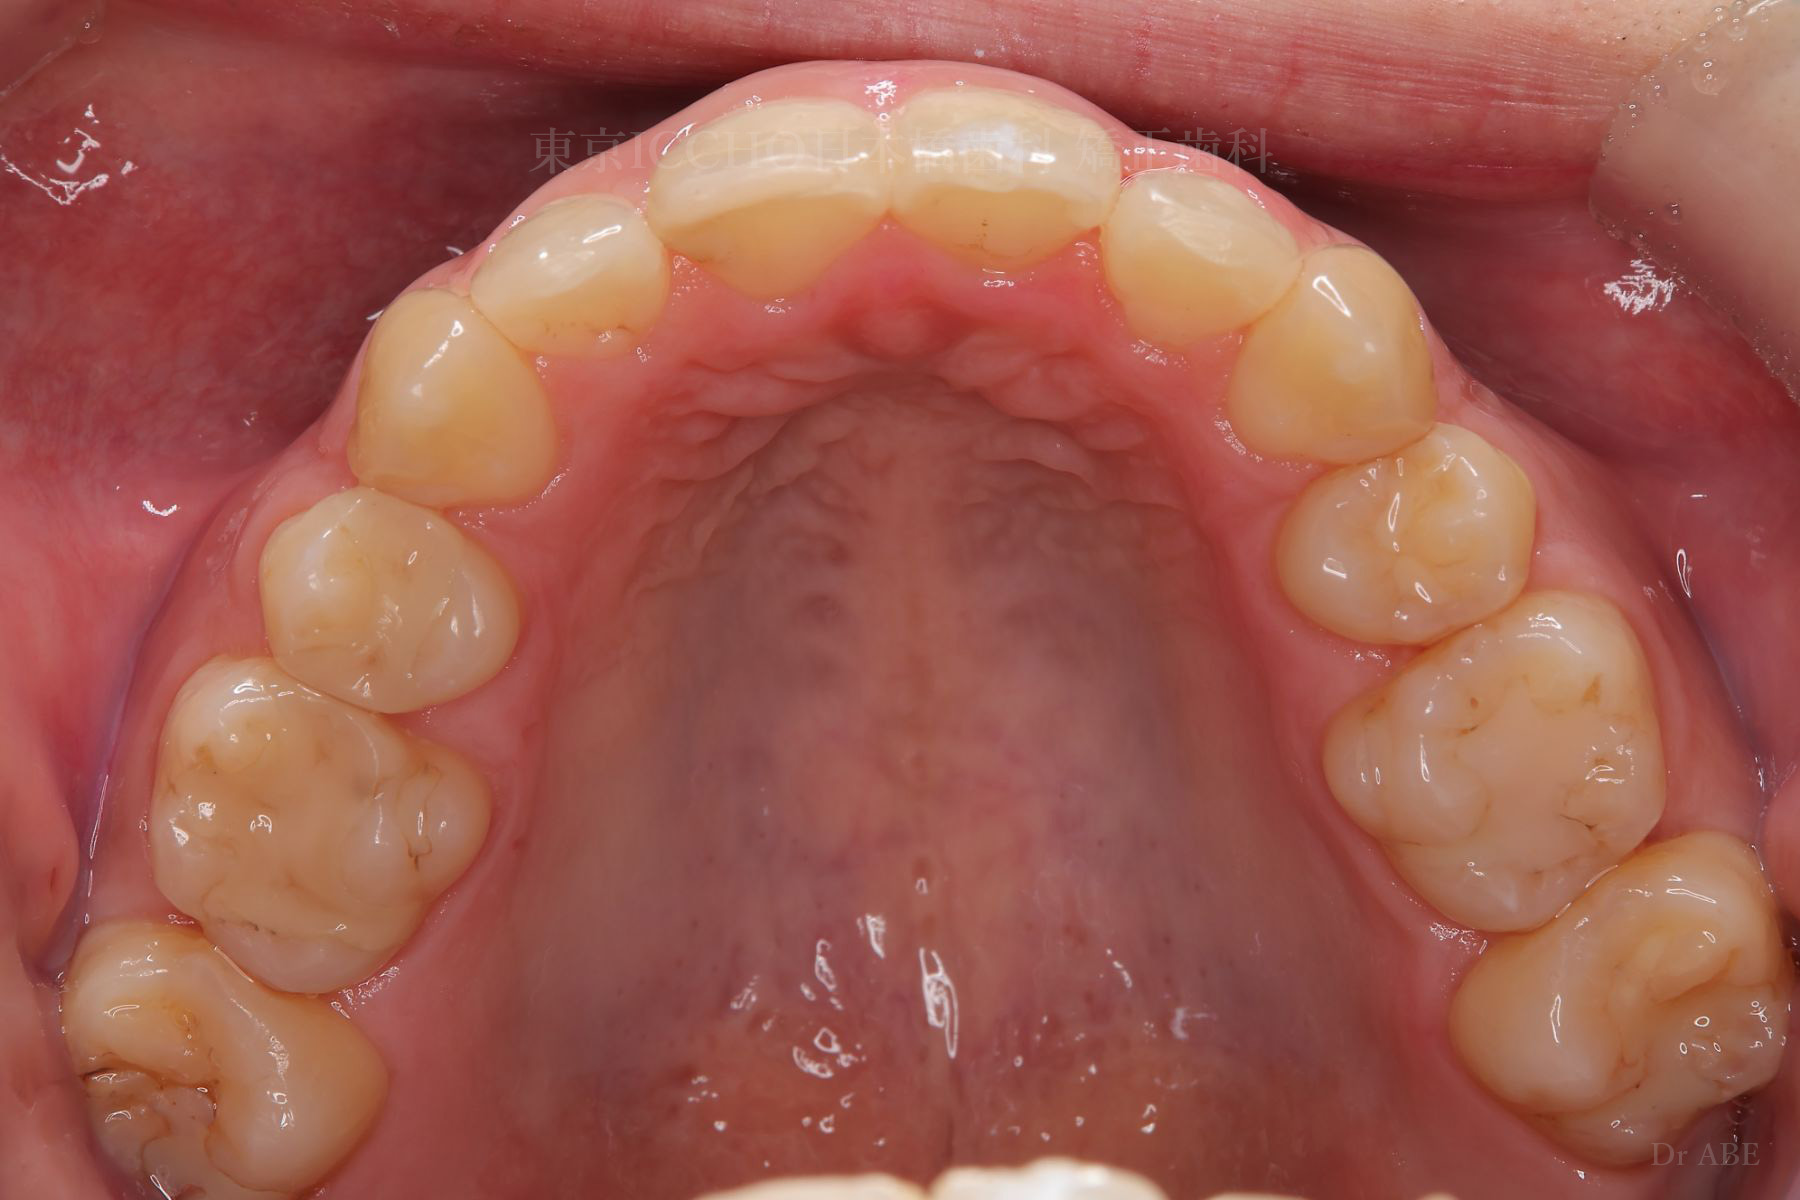

治療前

主訴 前歯が噛めないこと、出ているのを直したい。

治療内容 かみ合わせの不正と顎が小さいため、上下左右第一小臼歯4本の抜歯を行い前歯を後ろへ下げた。

また、前歯が噛まない状態のため、かみ合わせを少し下げて噛むように誘導し、全体的にかみ合わせとして機能的な矯正治療を行った。